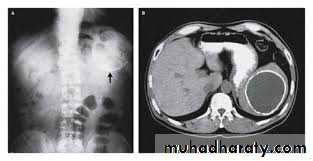

Splenic artery aneurysm

Aneurysms involving the splenic artery are estimated to occur at 0.04–1% of post-mortem examinations.They are twice as common in the female and are usually situated in the main arterial trunk. Although these are generally single, more than one aneurysm is found in a quarter of cases.

These may be a consequence of intra-abdominal sepsis and pancreatic necrosis in particular. They are more likely to be associated with arteriosclerosis in elderly patients.

The aneurysm is symptomless unless it ruptures and is more likely to be detected on a plain abdominal radiograph or ultrasound scan. It is unlikely to be palpable, although a bruit may be present.

Almost half the cases of rupture occur in patients younger than 45 years of age, and a quarter are in pregnant women, usually in the third trimester of pregnancy or at labour.

The treatment of choice previously consisted of splenectomy and removal of the diseased artery. Some surgeons advocate ligation of the proximal and distal ends of the sac to allow thrombosis of the aneurysm and partial or completelay.

Embolisation or endovascular stenting following selective splenic artery angiography can be considered

Splenic artery aneurism